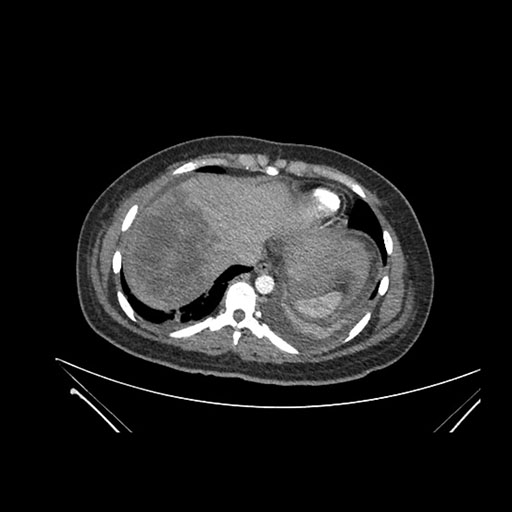

Axial Arterial